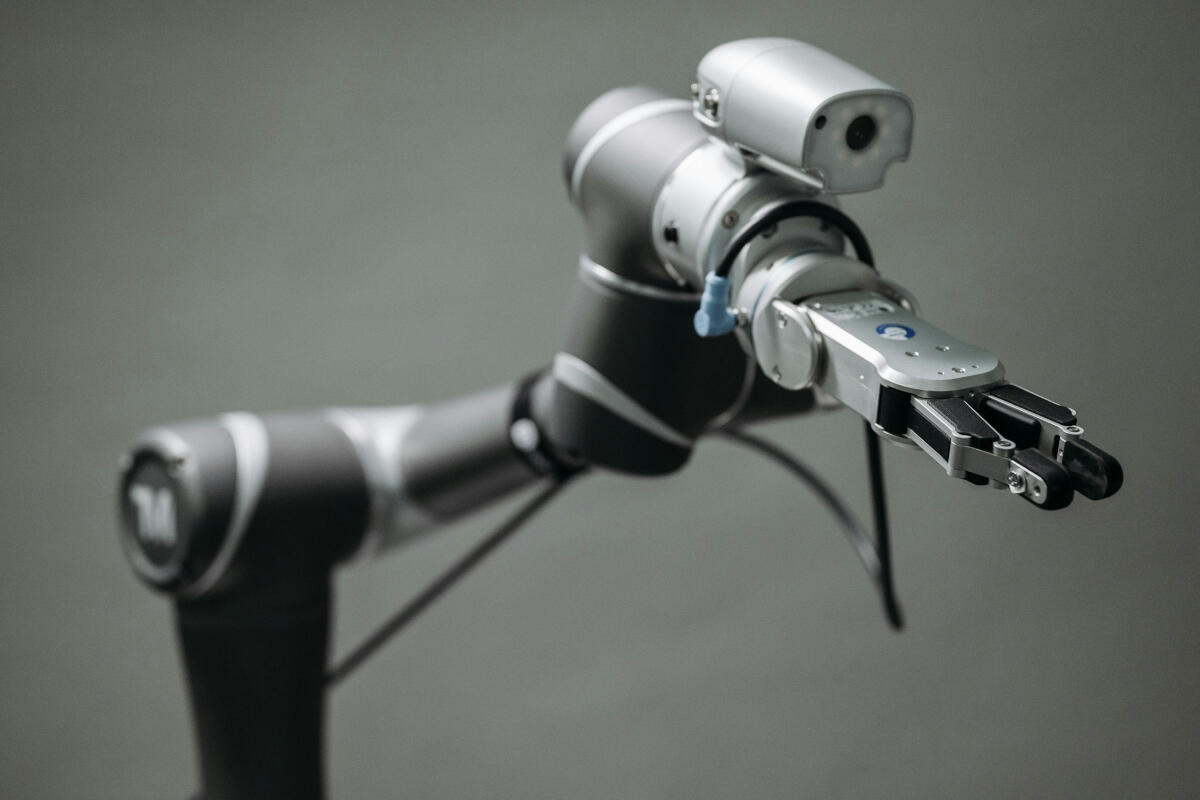

Ricostruire un ginocchio con una protesi in poco più di un’ora? A Mestre è possibile al Policlinico San Marco attraverso il sistema robotizzato Rosa che utilizza algoritmi di intelligenza artificiale per affiancare i chirurghi nelle operazioni. I medici guidano gli interventi e decidono tagli e operazioni, ma la tecnologia consente una precisione millimetrica e una perfetta replicabilità dell’applicazione di protesi. «Al momento siamo gli unici sul territorio veneziano a offrire questo tipo di intervento – spiega il dottor Gianluca Novello, Dirigente Medico presso l’Unità Operativa di Ortopedia – in una mattina grazie al nostro robot possiamo installare fino a 8 protesi alle ginocchia in circa un’ora di intervento, di cui 20 minuti vanno per la sola suturazione».

«Se le ossa sono sane si cerca di fare il possibile per ricostruirle – aggiunge il sanitario – ma oggi si ricorre spesso in maggior sicurezza alle protesi nei casi di interventi su anziani, complice l’allungamento della longevità e il conseguente innalzamento dell’età media dei pazienti. Non è un caso che dal punto di vista degli interventi le fratture al collo del femore siano ormai in larga parte risolte col ricorso all’applicazione di una protesi. Infatti dove si trova un’usura articolare importante è inutile fare tentativi rischiosi, soprattutto se si può utilizzare una tecnologia di frontiera come la chirurgia ortopedica robotica che, nel caso degli interventi al ginocchio al Policlinico San Marco, permette di avere dopo solo due ore un paziente in piedi». I vantaggi dell’uso di protesi inoltre si concretizzano anche nella manutenzione, visto che riguardo la preoccupazione della loro sostituzione nel tempo va ricordato che il re-impianto è possibile a seguito del primo intervento di applicazione.